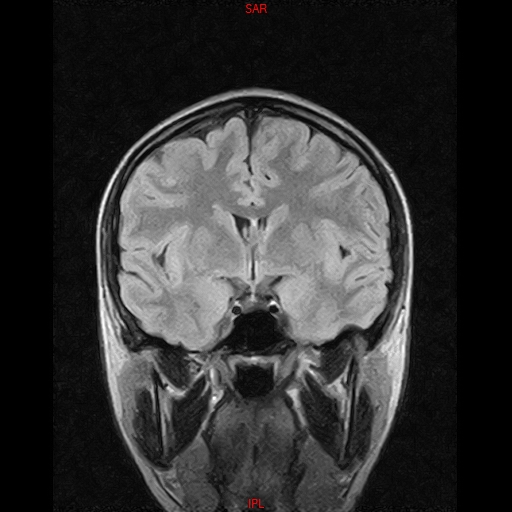

• Resonancia NORMAL CRANEAL T2 AXIAL

• Resonancia NORMAL CRANEAL T1 AXIAL